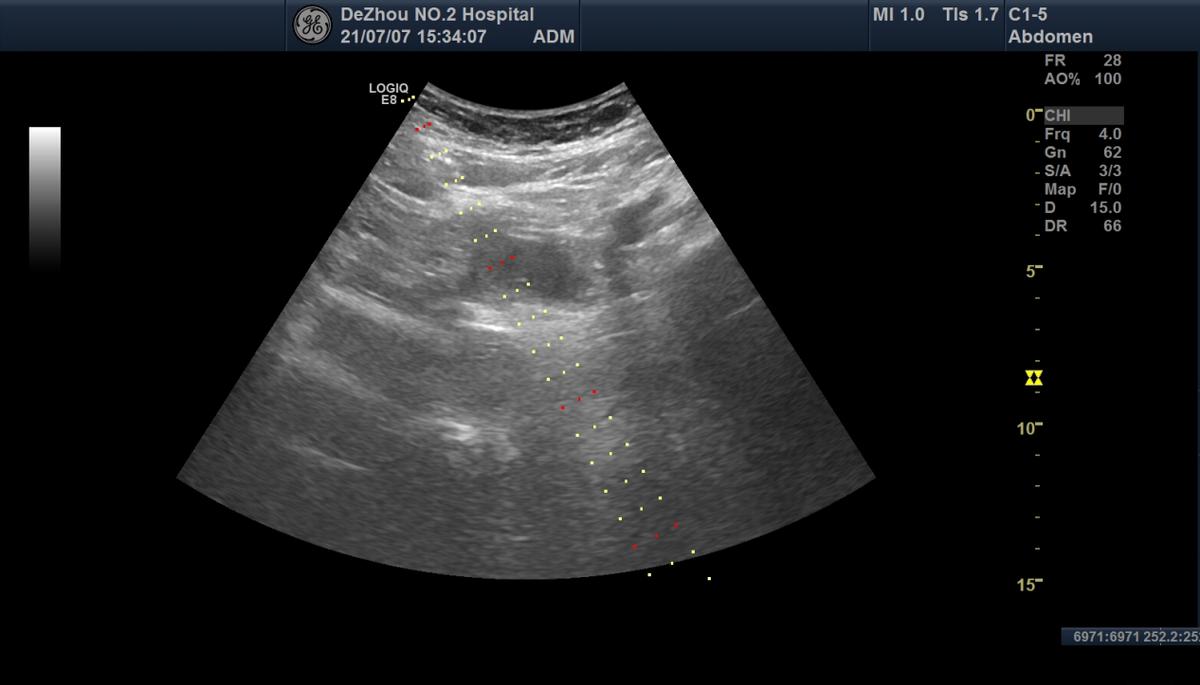

抽尽囊液

冲洗囊腔